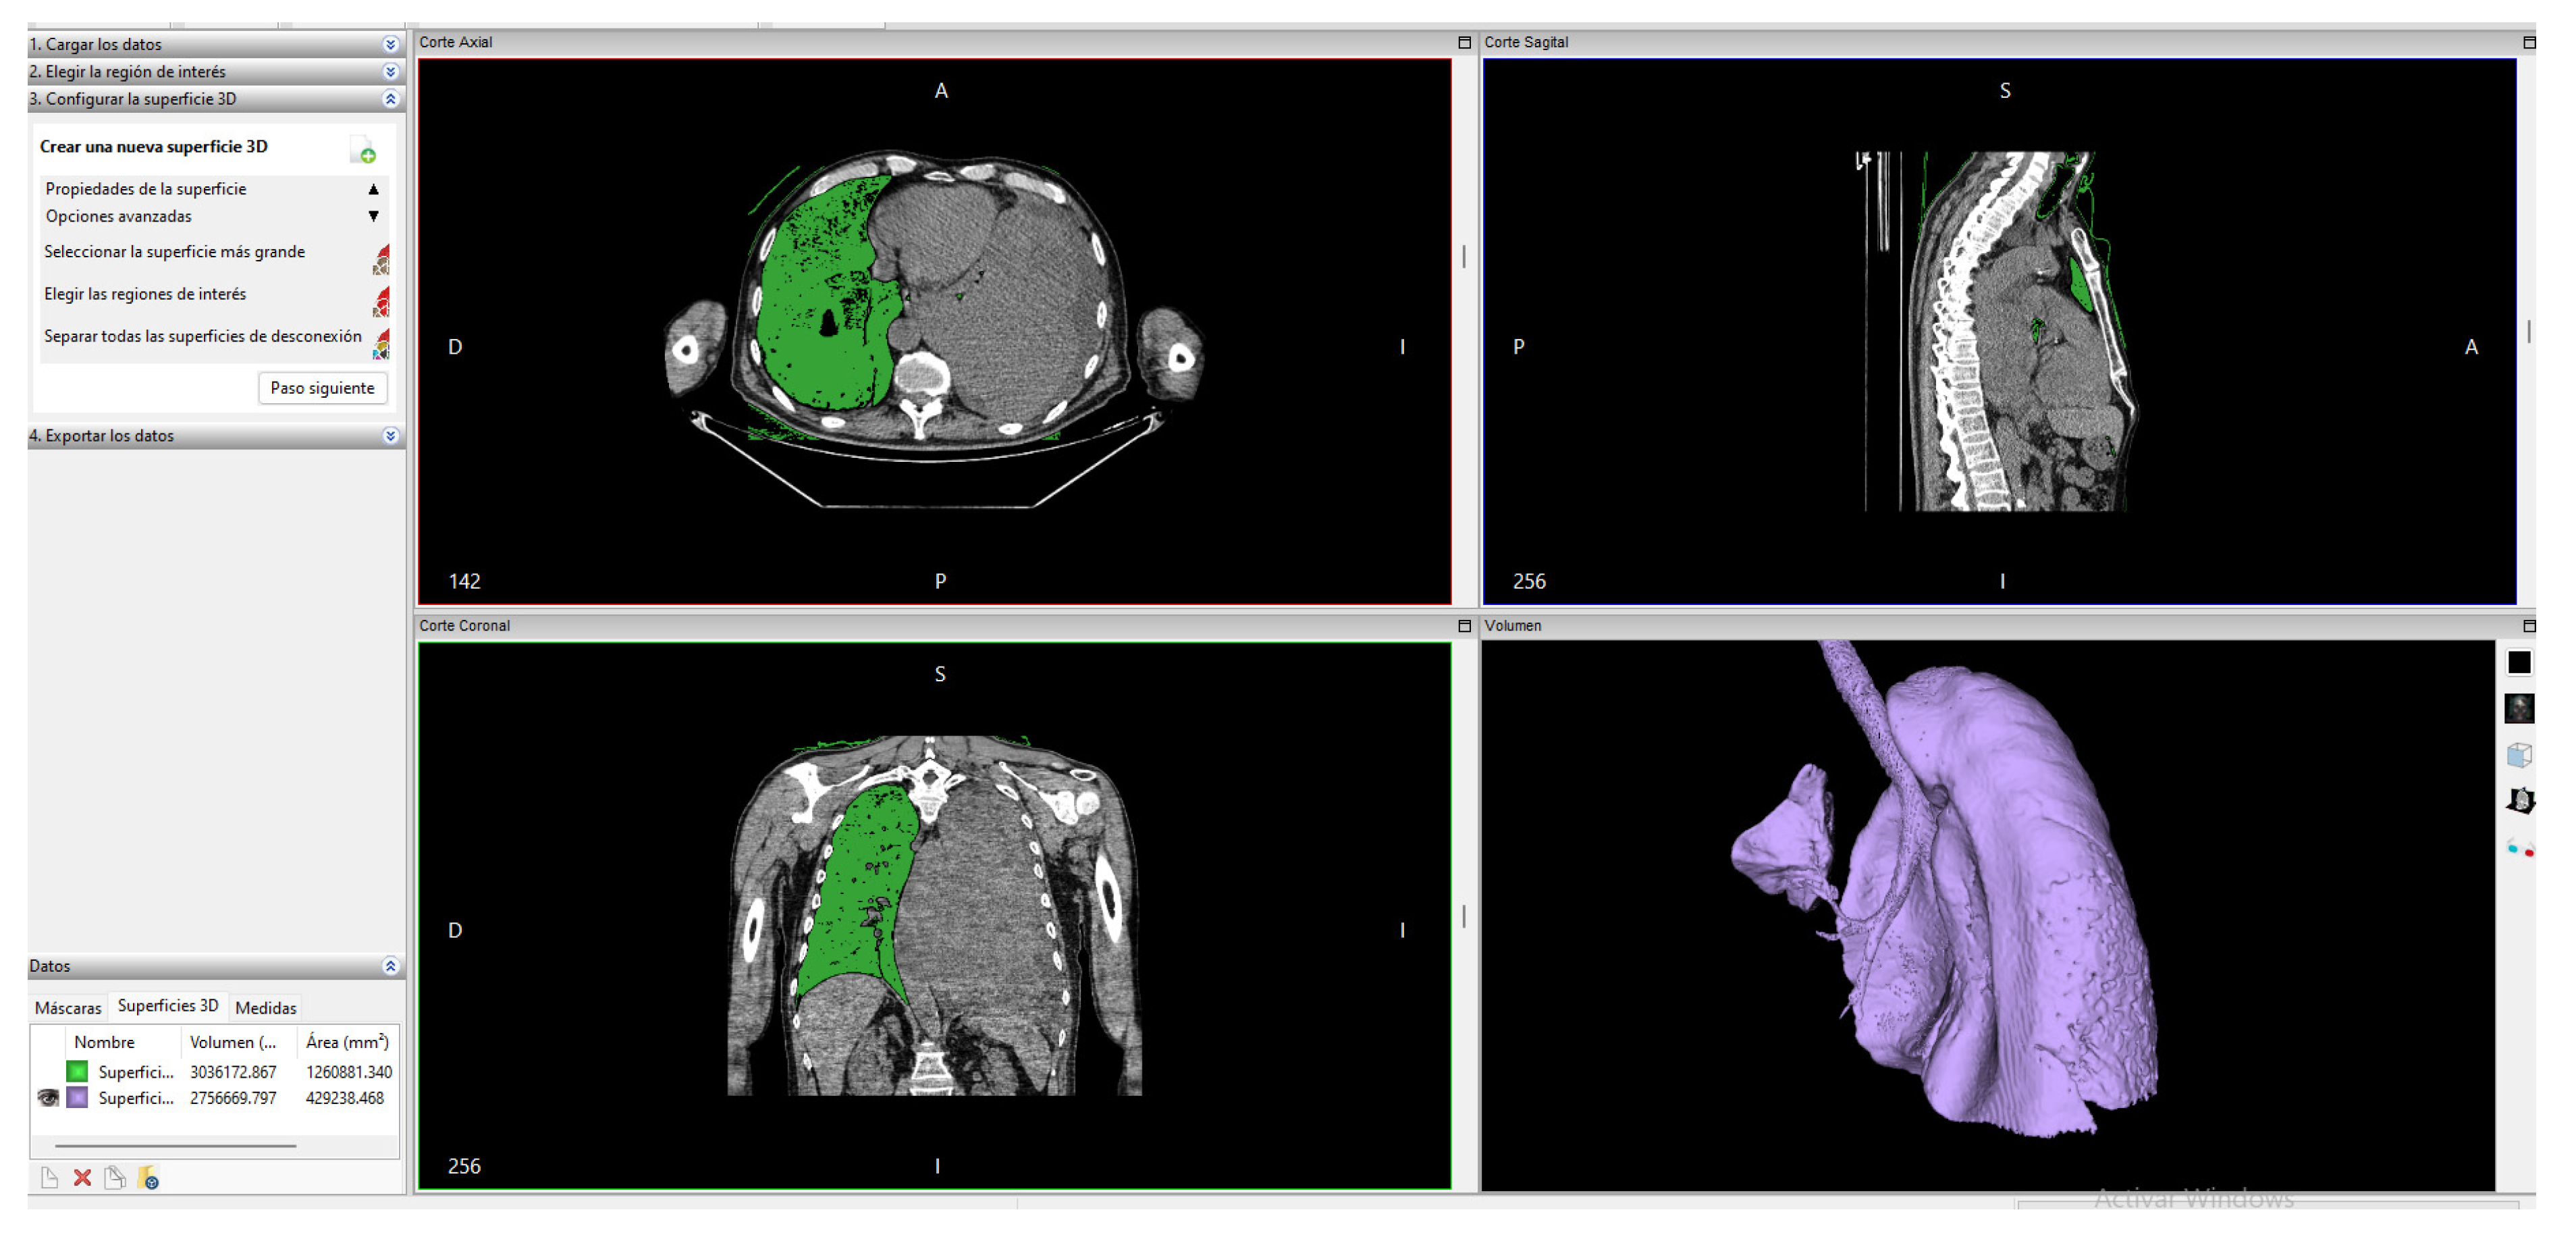

2.3.2. Invesalius

2.3.3. ITK-Snap